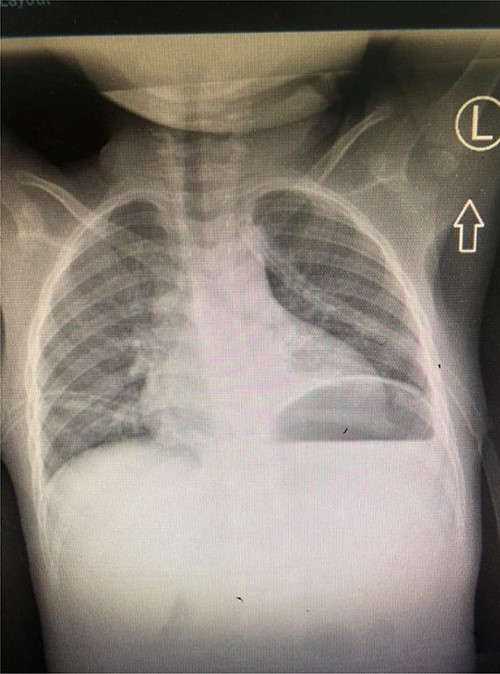

Dissection of the lesion was done with no major damage to the neurovascular or respiratory structures. The thoracic duct was injured, identified and ligated. The patient recovered well post-anesthesia and surgery, and was sent to surgical pediatric ward. At 18 hours post-surgery, she had progressive difficulty breathing, necessitating oxygen support through nasal prongs. Respiratory examination revealed reduced air entry bilaterally. Diagnostic needle thoracostomy was done, and it revealed milk-like fluid bilaterally. Chest tubes inserted bilaterally and drained a total of 250 ml of chyle (150 ml and 100ml), the latter being on the right side (Fig. 2). Drained fluid had higher triglyceride levels (130 mg/dl) than serum levels (80 mg/dl).

A total of 48 hours post tube thoracostomy patient had no drainage with complete resolution upon control X-ray (Fig. 4). She was then discharged and attended our outpatient department. She had an optimal recovery.

Control Chest X-ray showing resolution of the chylothorax with thoracostomy tubes in situ.